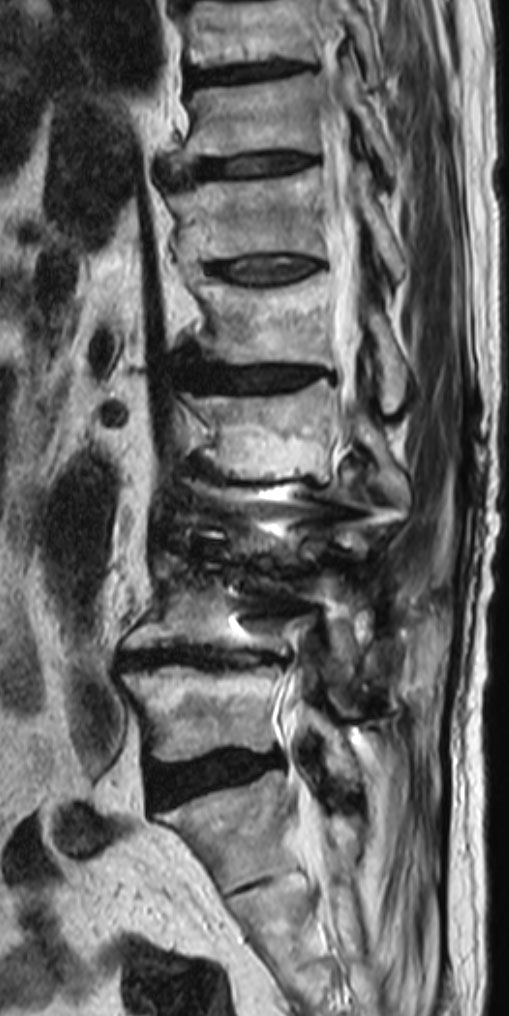

Sagittal T2w TSE O-MAR (VAT) 1